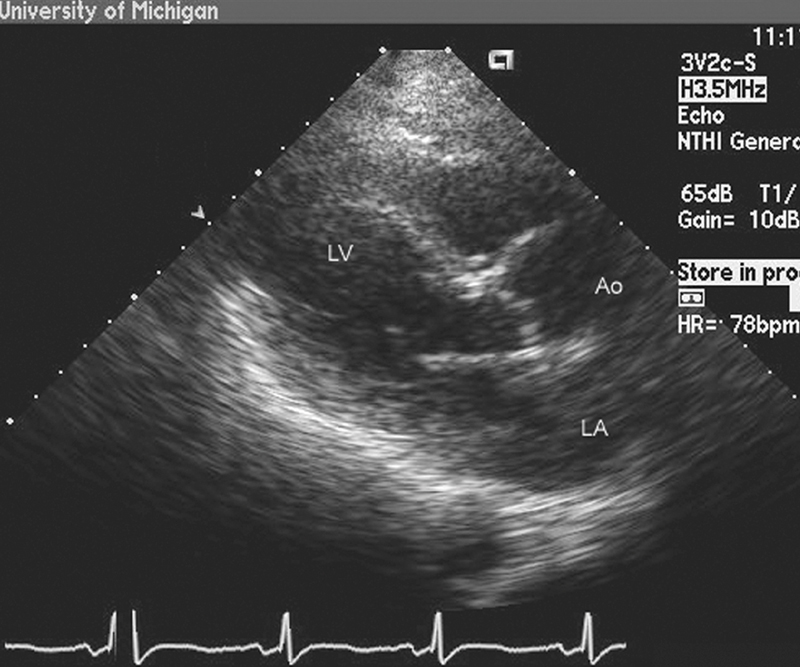

فحوصات تشخيصية لبعض امراض القلب والشرايين التاجية